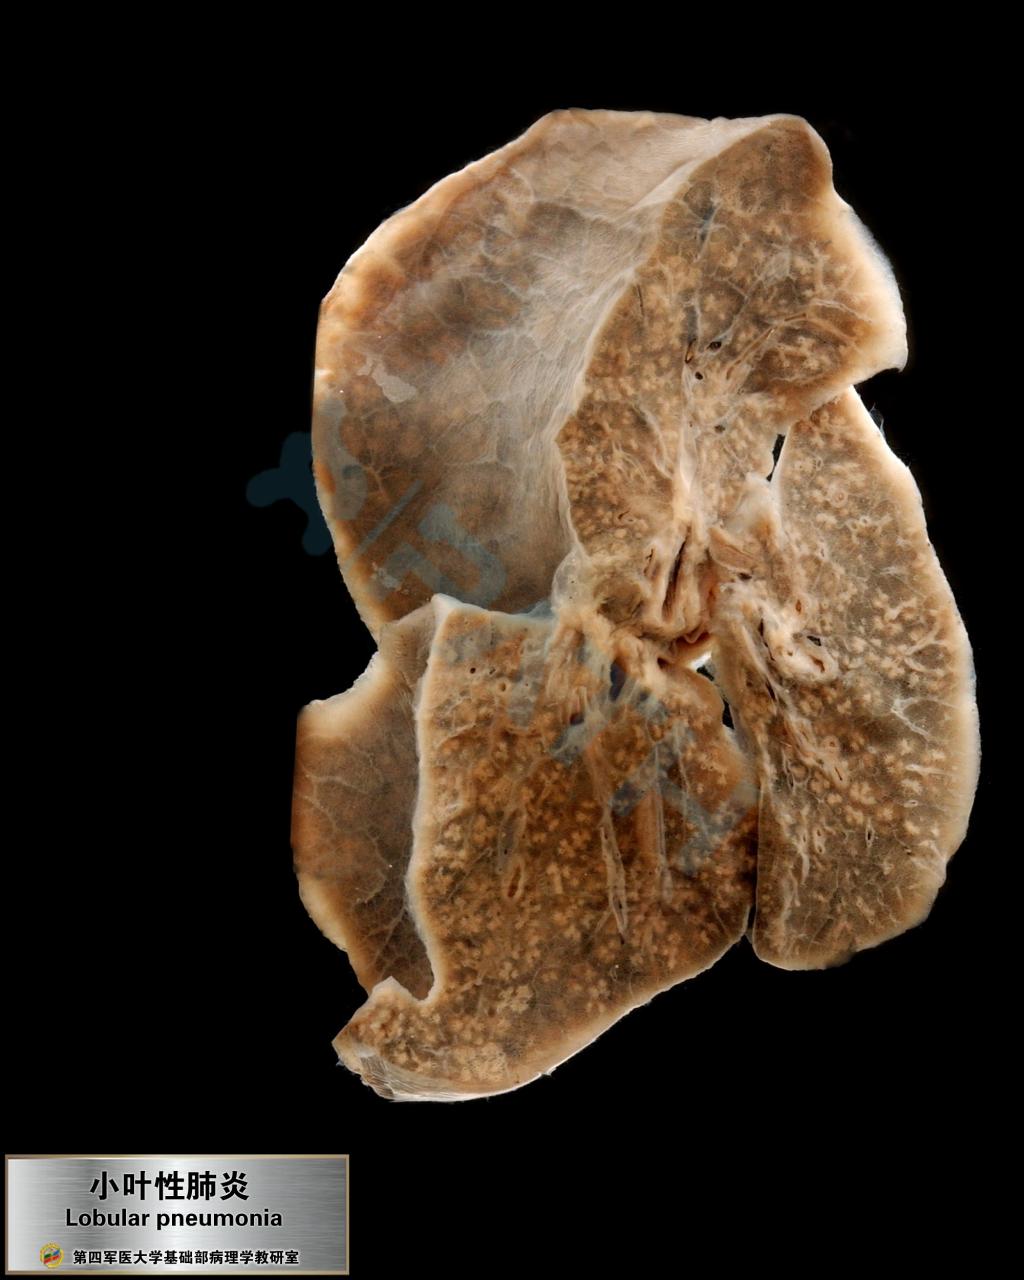

小叶性肺炎